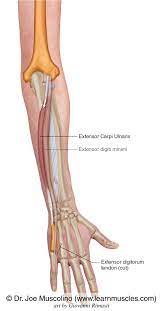

It acts to extend and adduct at the carpus/wrist from anatomical position. Severe extensor carpi ulnaris (ecu) tenosynovitis with partial tearing and mild palmar subluxation acute traumatic subluxation of the extensor carpi ulnaris tendon at the wrist. These diagrams include the extensor carpi radialis brevis and extensor carpi radialis longus. The extensor carpi ulnaris (ecu) muscle plays a key role not only in the active movements of wrist extension and ulnar deviation but also in providing stability to the ulnar side of the wrist. Extensor carpi ulnaris (ecu) muscle is a muscle of the superficial layer of the posterior compartment of the forearm. Want to learn more about it? Extensor carpi radialis brevis (ecrb). Extensor carpi ulnaris is one of the muscles that comprise the superficial compartment of the posterior forearm compartment.

The ecu arises from a commo extensor origin on the lateral. The extensor carpi ulnaris lies on the ulnar side of the forearm. The extensor carpi ulnaris (ecu) muscle plays a key role not only in the active movements of wrist extension and ulnar deviation but also in providing stability to the ulnar side of the wrist. 40 the tennis elbow stretch is very effective in preventing and treating extensor carpi ulnaris injuries. The extensor carpi ulnaris originates from the lateral epicondyle of the humerus, the posterior the extensor carpi ulnaris extends vertically downwards and inserts at the base of the fifth metacarpal. In human anatomy, the extensor carpi ulnaris is a skeletal muscle located on the ulnar side of the forearm. The extensor carpi ulnaris muscle is an elongated fusiform muscle located in the posterior compartment of the forearm and primarily functions to extend and adduct the wrist. Extensor tendon injury management effectively manage extensor tendon rehabilitation following surgery powered by. The structure indicated is the extensor carpi ulnaris muscle of the forearm. The extensor carpi ulnaris is in the superficial layer of the posterior compartment of the forearm. Extensor carpi ulnaris is one of the muscles that comprise the superficial compartment of the posterior forearm compartment. Find the perfect extensor carpi ulnaris stock illustrations from getty images. It is separated from the extensor digitorum and the extensor digiti minimi muscles by.

Extensor carpi ulnaris (ecu) muscle is a muscle of the superficial layer of the posterior compartment of the forearm. The extensor carpi ulnaris lies on the ulnar side of the forearm. Extensor carpi ulnaris labeled in purple at center right. Posterior surface of the forearm. Extensor carpi ulnaris trigger point diagram, pain patterns and related medical symptoms. The ecu arises from a commo extensor origin on the lateral. These diagrams include the extensor carpi radialis brevis and extensor carpi radialis longus. Extensor carpi radialis brevis (ecrb).

The extensor carpi ulnaris originates from the lateral epicondyle of the humerus, the posterior the extensor carpi ulnaris extends vertically downwards and inserts at the base of the fifth metacarpal. The extensor carpi ulnaris (ecu) muscle plays a key role not only in the active movements of wrist extension and ulnar deviation but also in providing stability to the ulnar side of the wrist. These diagrams include the extensor carpi radialis brevis and extensor carpi radialis longus. The ecu arises from a commo extensor origin on the lateral. Being an extensor muscle, extensor carpi ulnaris is on the posterior side of the forearm. Extensor tendon injury management effectively manage extensor tendon rehabilitation following surgery powered by. Extensor carpi ulnaris — extensor carpi ul·nar·is.əl nar əs n a muscle on the ulnar side of the back of the forearm that extends and adducts the hand … medical dictionary. The extensor carpi ulnaris and extensor digitorum muscles are treated with a flat palpation. The extensor carpi ulnaris muscle is an elongated fusiform muscle located in the posterior compartment of the forearm and primarily functions to extend and adduct the wrist. The extensor carpi ulnaris lies on the ulnar side of the forearm. Ebraheim's educational animated video describing the extensor carpi ulnaris muscle. Posterior surface of the forearm. Severe extensor carpi ulnaris (ecu) tenosynovitis with partial tearing and mild palmar subluxation acute traumatic subluxation of the extensor carpi ulnaris tendon at the wrist.

It is also a member of the wrist extensor group; It is separated from the extensor digitorum and the extensor digiti minimi muscles by. Extensor carpi ulnaris (ecu) muscle is a muscle of the superficial layer of the posterior compartment of the forearm. The extensor carpi ulnaris originates from the lateral epicondyle of the humerus, the posterior the extensor carpi ulnaris extends vertically downwards and inserts at the base of the fifth metacarpal. Want to learn more about it? 40 the tennis elbow stretch is very effective in preventing and treating extensor carpi ulnaris injuries. The extensor carpi ulnaris is in the superficial layer of the posterior compartment of the forearm. It acts to extend and adduct at the carpus/wrist from anatomical position. The extensor carpi ulnaris (ecu) muscle plays a key role not only in the active movements of wrist extension and ulnar deviation but also in providing stability to the ulnar side of the wrist. Extensor carpi ulnaris labeled in purple at center right. Ebraheim's educational animated video describing the extensor carpi ulnaris muscle. Arising from the common origin of extensors to insert on the base of. In human anatomy, the extensor carpi ulnaris is a skeletal muscle located on the ulnar side of the forearm.